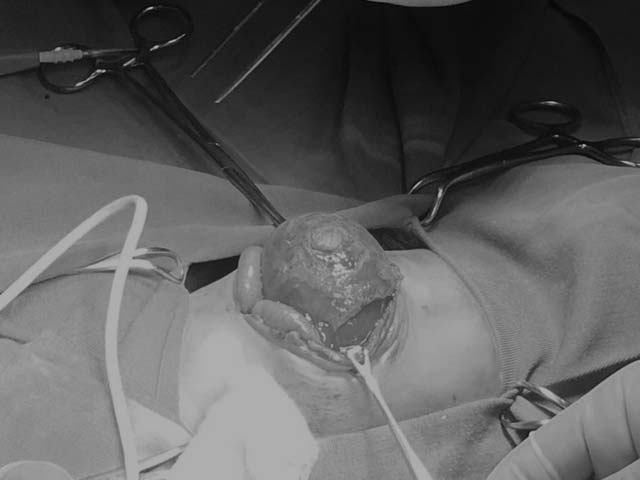

Phần nội tạng của cháu bé bị tràn ra ngoài thành bụng.

Trong quá trình theo dõi, kết quả siêu âm ổ bụng cháu T. cho thấy, có hình ảnh khối thoát vị. Kiểm tra ngoài thành bụng có khối thoát vị thành bụng kích thước 5x8cm, bề mặt khối thoát vị bắt đầu hoại tử.

Ca phẫu thuật diễn ra trong khoảng hơn 40 phút, các bác sĩ tiến hành cắt bỏ toàn bộ tổ chức hoại tử trên bề mặt khối thoát vị, đưa khối ruột của bé vào đúng vị trí và tiến hành khâu phục hồi thành bụng 1 lớp cho trẻ.

Các bác sĩ đang tiến hành phẫu thuật cho bé T.